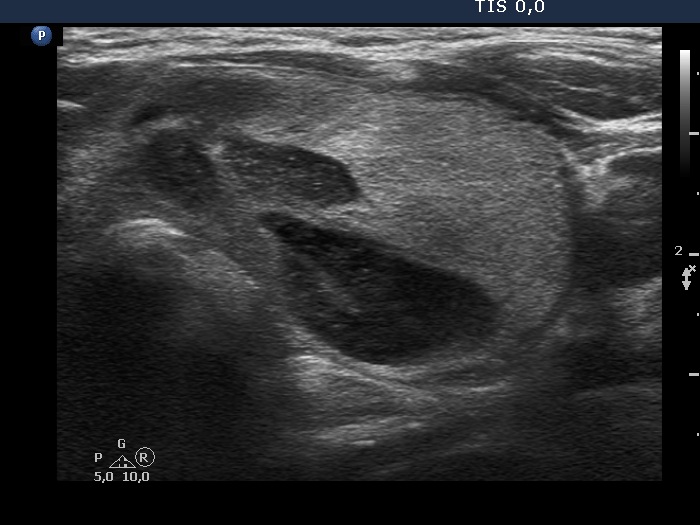

The borders of the nodule - case 2152 (ultrasonographic picture 6)

Left lobe, another transverse view.